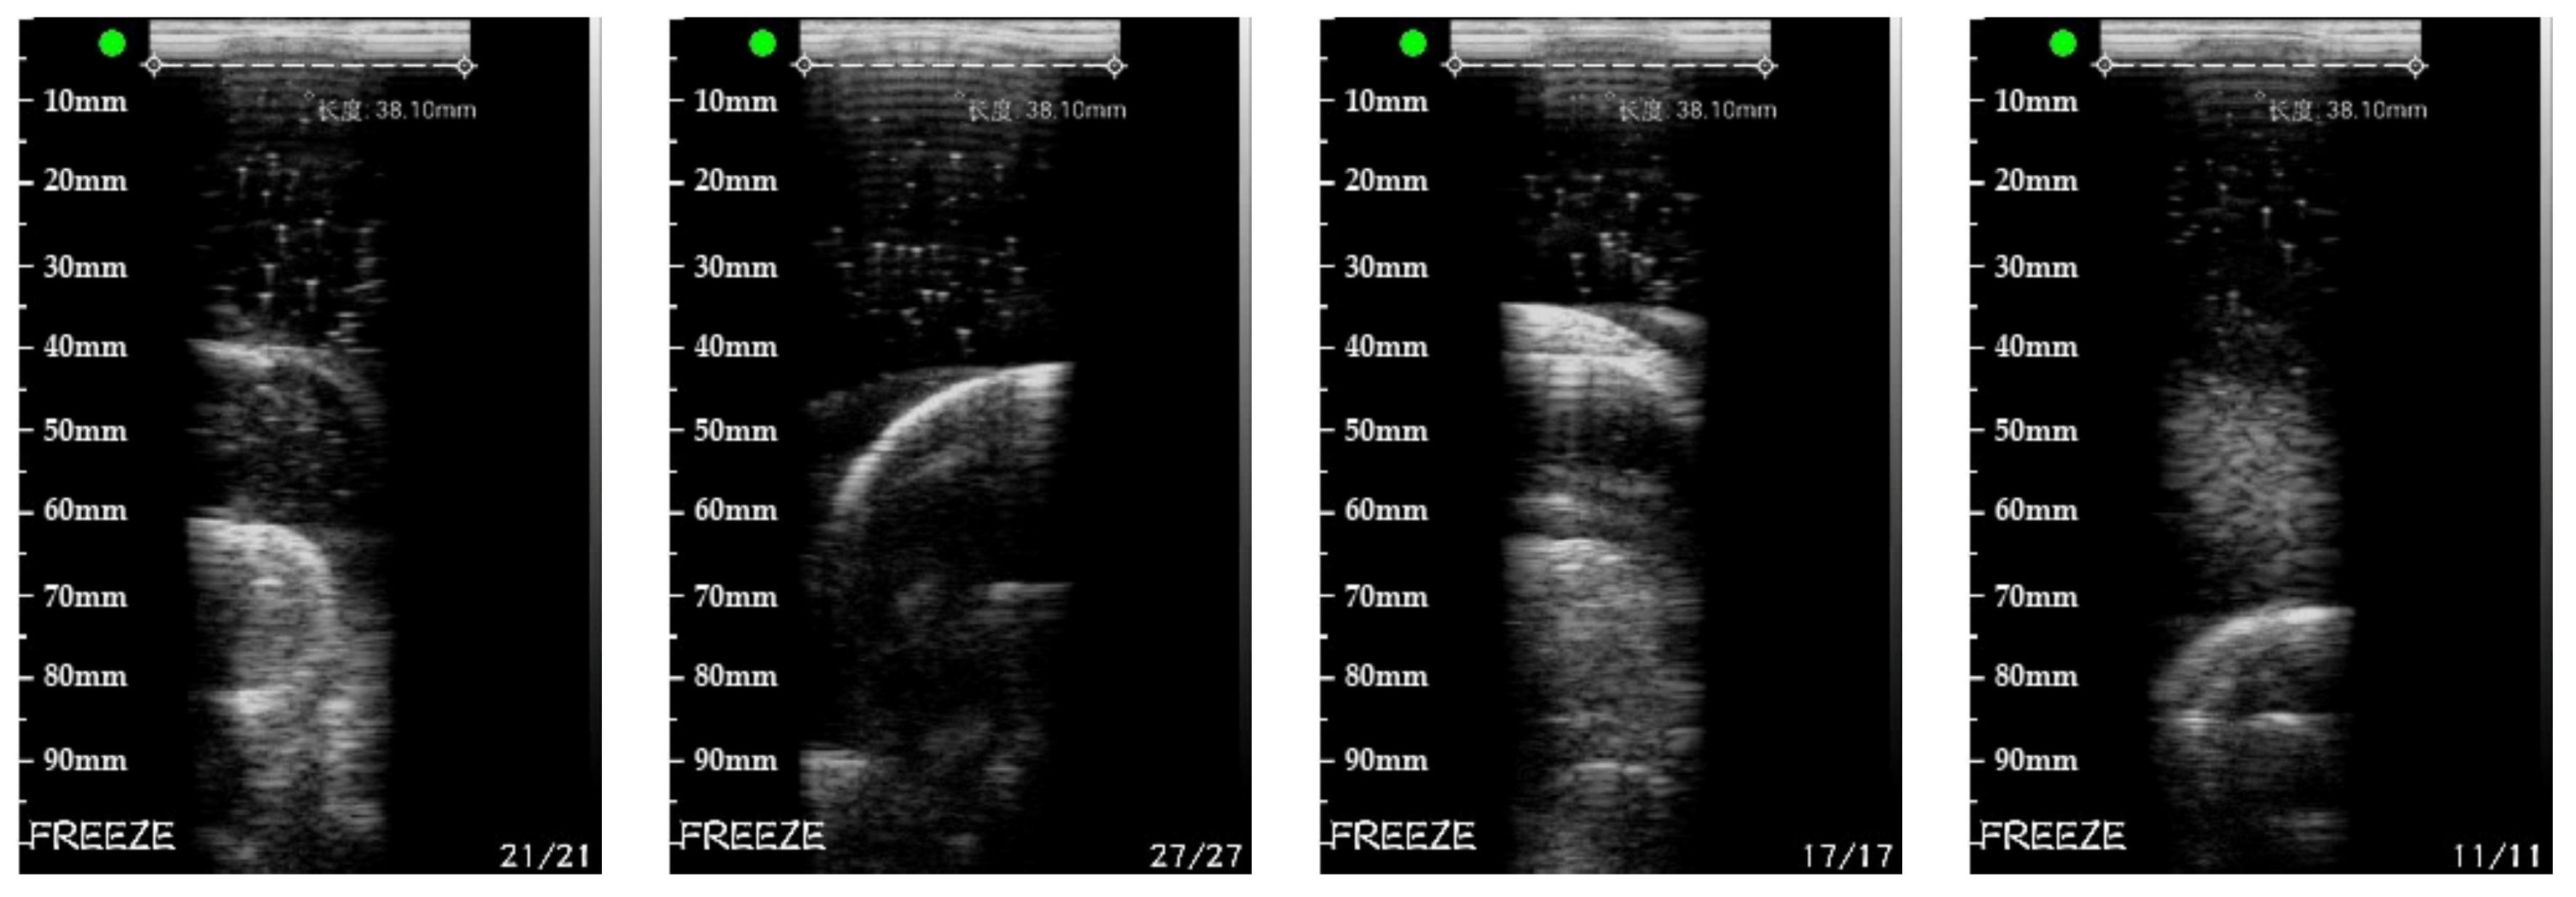

5.3. Real Target Reconstruction Result